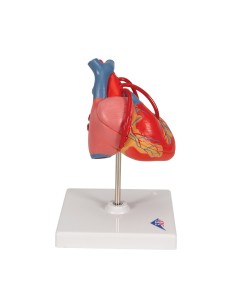

Du crâne en 22 parties à verrouillage magnétique aux modèles de colonne vertébrale, des modèles d'articulation aux modèles de cœur, chaque pièce de notre collection est conçue pour une immersion totale dans l'étude de l'anatomie humaine. Nos modèles, réalisés à partir de scans d'os réels, garantissent une expérience tactile authentique et une fidélité de poids presque identique aux originaux.